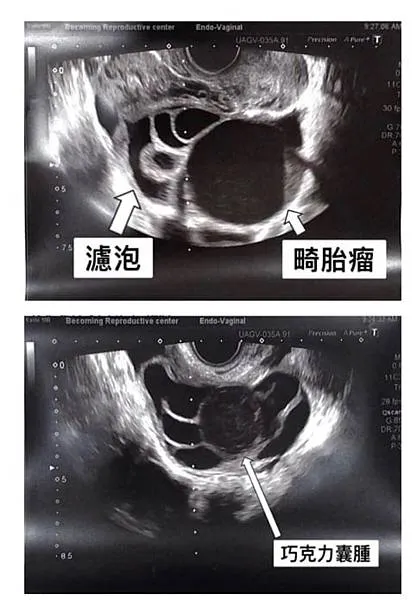

這週我有兩位入療者,一位33歲,右卵巢有一顆五公分的巧克力囊腫,她的AMH是4.2。另外一位35歲,左卵巢有一個6.5公分的畸胎瘤,AMH是5.1。這兩位,取卵前除了刺激排卵的藥物以外,我並沒有給予其他的藥物或手術治療。但兩位患者在用藥刺激排卵的過程中,即使有腫瘤側的卵巢也有良好的反應,產生足夠數量的濾泡,而且在取卵時也能取到成熟的卵子。只是我在取卵過程中需要避免穿刺到卵巢上有腫瘤的部位。之後在實驗室進行培養,這些卵子也能正常受精、分裂、發育至囊胚期。

所以如果是年輕女性,AMH值良好,即使有卵巢囊腫還是可以使用排卵藥物刺激,進行取卵。